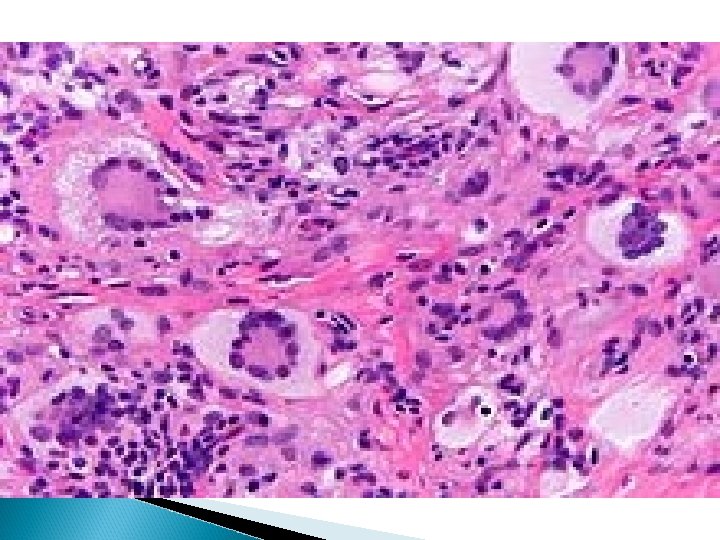

Morphology Caseating granuloma (tubercle): focus of activated macrophages (epithelioid cells), rimmed by fibroblasts, lymphocytes, histiocytes, occasional Langhans giant cells; central necrosis with amorphous granular debris; acid-fast bacilli

�A granuloma is a microscopic aggregation of macrophages that are transformed into epithelioid cells and giant cells surrounded by a collar of mononuclear leukocytes, principally lymphocytes and occasionally plasma cells

CELLS IN GRANULOMAS *Macrophages are almost all recruited directly from the bloodstream monocytes. *Epithelioid cells have abundant pink cytoplasm, indistinct borders, and elongated 36

The giant cells 40 to 50 µ in dia -abundant cytoplasm, multiple nuclei. *Plasma cells produce antibodies against the persistent antigen or the altered tissue components. *Lymphocytes are likely to be present even where there is no involvement of the immune system.